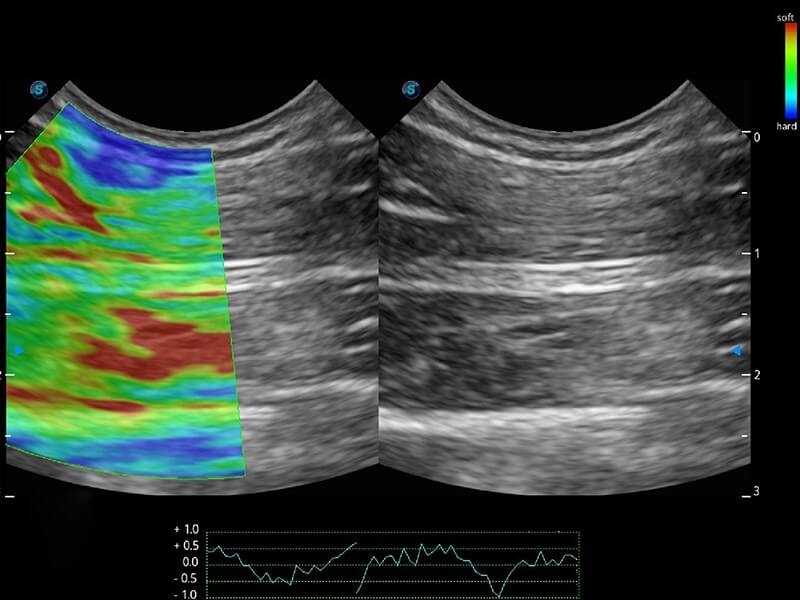

ProPet 60 作为一款高端台式动物超声设备,为动物医生的日常诊断提供了一系列贴合动物临床需求、解决临床实际问题的高级成像功能。凭借全系列高清探头,满足医生对腹部、心脏、生殖、浅表、肌骨等成像的所有需求,切实帮助您提升检查效率,提高诊断信心。

兽用彩色多普勒超声诊断系统